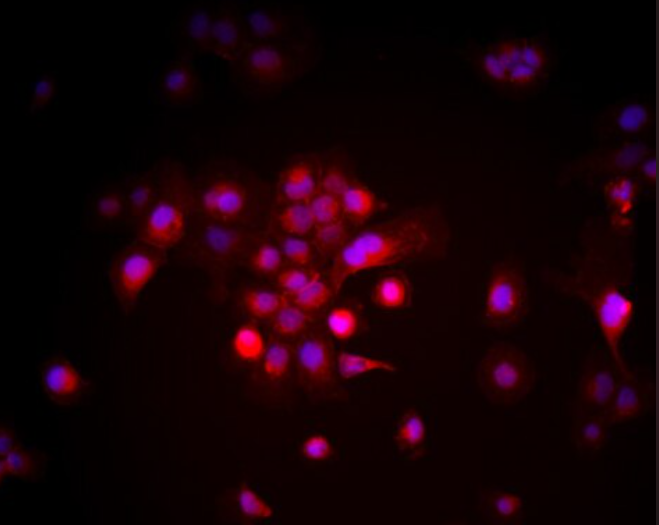

小鼠腮腺细胞,Mouse parotid gland cells

中文名称:小鼠腮腺细胞英文名称:Mouse parotid gland cells

细胞系: 小鼠腮腺细胞

小鼠腮腺细胞(Mouse Salivary Gland Cells)来源于小鼠腮腺组织,常用于腮腺发育、腮腺癌及药物筛选研究。腮腺细胞在体外能够长时间传代并保持其腮腺特异性功能,如表达腮腺特征性标志物Amylase、CK18等。腮腺细胞在腮腺发育、腮腺癌研究和新药筛选中具有重要应用。